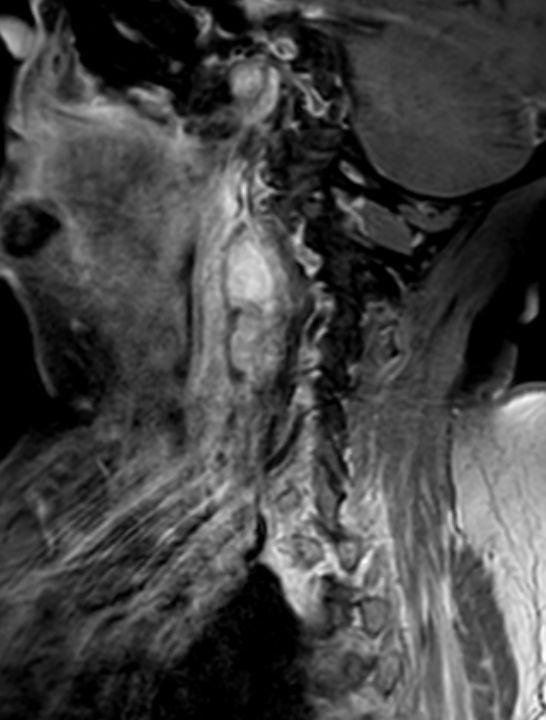

| Diagnostik | 88-jährige Frau mit einer progredientes

Dysphagie. Es besteht eine Raumforderung rechts retropharyngeal. Mukosa intakt.![]() |